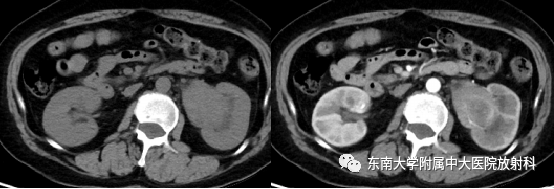

肾盂癌分型及其鉴别诊断

病例

女,52岁

主诉:肉眼血尿1年

现病史:患者无明显诱因下出现肉眼血尿,阵发左侧腰疼,无尿频尿急,于当地医院就诊查彩超结果无特殊,后多次复查影像学结果无特殊,症状无好转